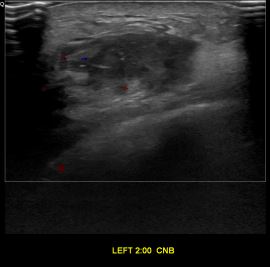

상기환자는 좌측 유방 만져지는 멍우리있어  내원하신 40대 초반

여성분으로 의심스러운 좌측유방혹 조직검사 시행해 유방암으로 진단되었습니다